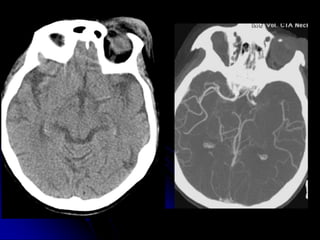

• HEAD/CSPINE

• Non contrast

• 1mm acquisition, displayed thicker

• Coronal, sagittal reformats

C-SPINE IMAGING

ALGORITHM

• CT

• MRI (depending upon Hx, PE, CT

findings)